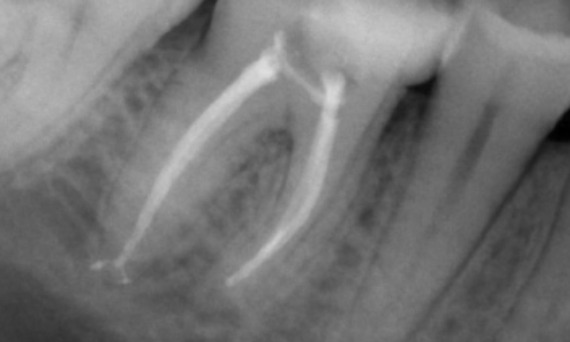

Önce: Öncelikli olarak distal kökle ilişkili periyapikal radyolüsen ve mesiyal kökte lamina dura kaybı.

Sonra: TruNatomy, bu vakada çürüklerden yararlanılan bir yaklaşıma ve özellikle dişin daha minimal bir restorasyona sahip olduğu mesiyal yönde periservikal dentin korumasına odaklanmaya izin vermek için seçilmiştir.